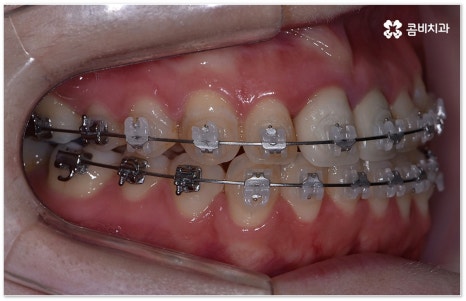

요즘 가장 많이 쓰이는 치아교정장치 인 클리피씨는 치아 색상의 세라믹 브라켓을 이용하기 때문에 심미성도 뛰어나고 자가결찰방식을 이용하여 보다 적은 힘으로 지속적이고 부드러운 치아 이동을 할 수 있도록 고안된 장치이므로 통증을 줄여줄 뿐 아니라 보통 2년 남짓 걸렸던 전체 교정 기간 역시 6개월 정도 감소시켜 줄 수 있습니다. 환자분들의 상황에 따라 내원 횟수 역시 줄일 수 있기 때문에 업무가 많이 바쁜 직장인분들의 경우에도 이용할 수 있다는 장점을 가지고 있어요.

부정교합을 개선할 때 교합이 어긋난 정도가 심하고 구조적인 원인이 커서 부분 교정이 아닌 전체 교정이 필요한 케이스인 경우라고 해도 말씀드렸던 클리피씨 교정 장치 또는 보다 심미성을 강조한 치아교정장치 들의 도움을 통해 다른 사람과 얘기를 하거나 음식을 먹을 때 브라켓이 두드러지게 드러나는 부담을 줄일 수 있으니 설측교정, 콤비교정, 투명교정, 인비절라인 등에 대해서 한 번 알아보시고 각자에게 맞는 방법으로 교정 치료를 시작해 보시길 권유드리고 있어요.